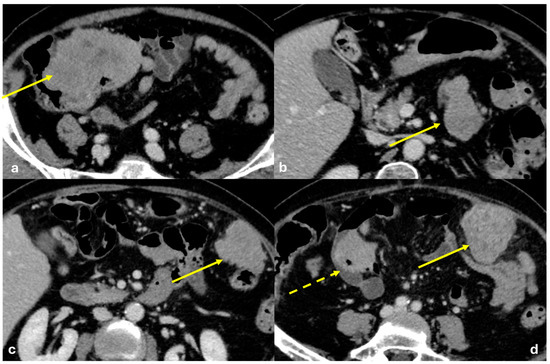

- Nodular pattern: nodules with a diameter > 5 mm (Figure 2a);

- “Omental cake”: nodular thickening of the omentum (Figure 2b);